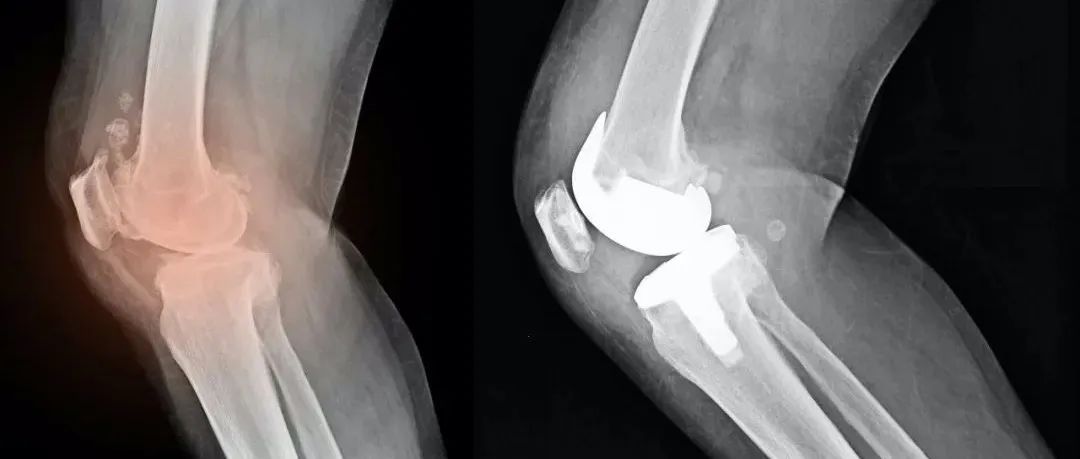

你知道痛风石有这4种手术治疗方法么?

本文未经允许禁止转载痛风是单钠尿酸盐沉积在组织所致的疾病,与嘌呤代谢紊乱导致的高尿酸血症密切相关。单钠尿酸盐可发生体外结晶从而引起周围组织反复的慢性类肉芽肿反应,最终形成由单钠尿酸盐晶体、炎症细胞以及纤维组织构成的慢性痛风石 。不同解剖位置的痛风石会出现不同的临床症状,位于关节肌腱处的痛风石可导致不可逆的肌腱、关节损伤和骨质破坏,位于周围神经处可出现卡压症状。痛风最重要的治疗是降低血尿酸水平,手术应该是痛风治疗的最后选择,但也有仍一部分难治性痛风患者血尿酸水平控制不佳、发作频繁,为改善这部分患者的生活质量可考虑手术治疗。...